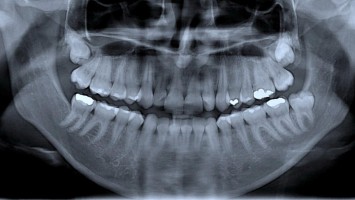

S2k-Konsensus-Leitlinie zur systemischen Sklerose vorgestellt

Erstmals gibt es auch eine deutsche Leitlinie zur Diagnostik und Behandlung bei systemischer Sklerose (SSc). Eine Besonderheit ist, dass sie auch ein Kapitel zur Zahn-, Mund- und Kiefergesundheit und eines zu Sexualität und Schwangerschaft enthält.